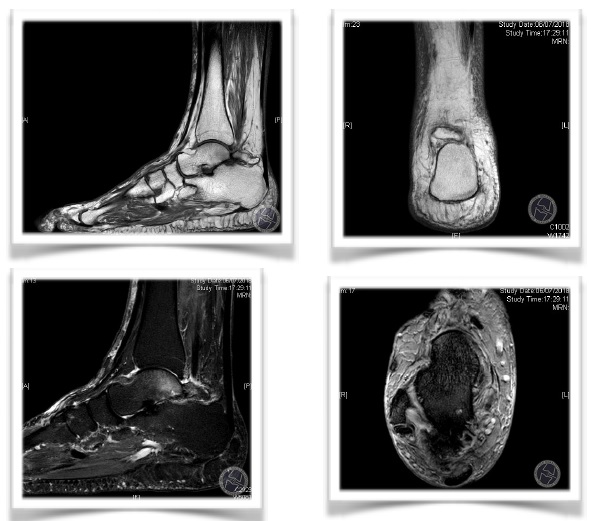

ESTUDIO POR IMAGEN: RMN

Confirmación de OS TRIGONUM en las secuencias T1 y T2

Lesion osteo-condral (LOC) en la cúpula astragalina en la zona 6.

Edema óseo en la region posterior del astrágalo.

Artrosis subastragalina